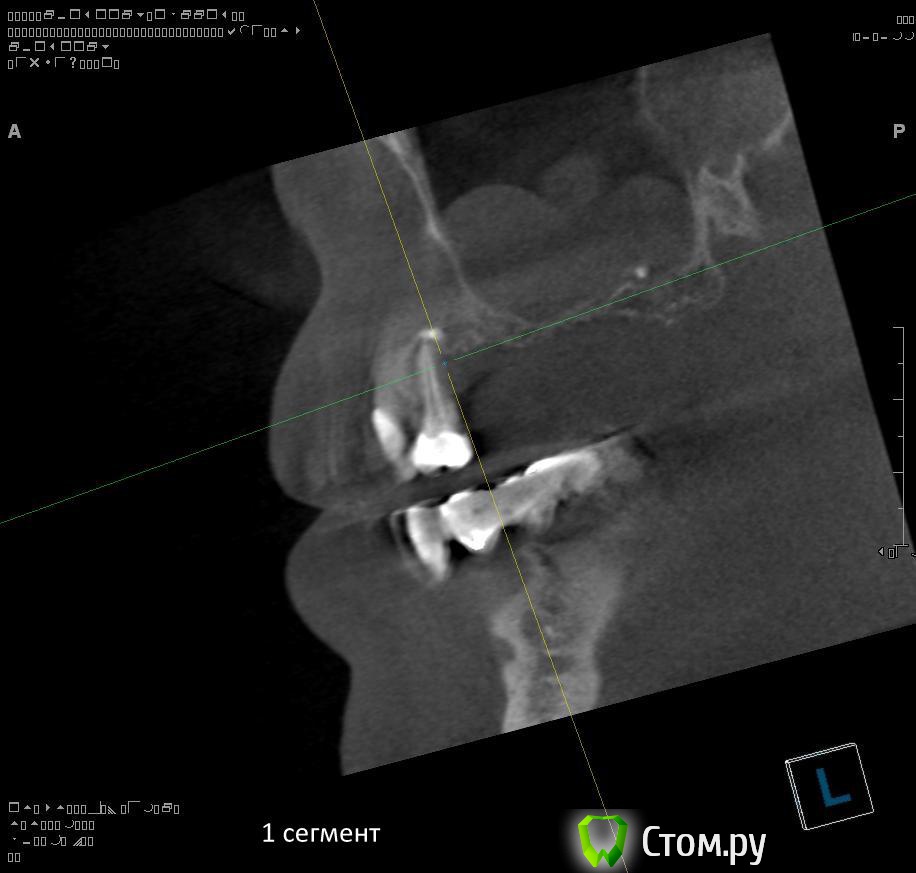

Провели обследование. Ортопед планирует оставить вверху 6 фронтальных зубов (возможно резцы пойдут на удаление), внизу только клыки. Далее последует удаление несостоятельных зубов + иммедиат протезы, продолжение реабилитации.

1. правильно ли я понимаю, что через 1,5 - 2 месяца после удаления 1.4 можно провести аугментацию (синус-лифтинг, латеральное окно, в первом сегменте, возможно с одномоментной установкой имплантатов)?

2. нужна ли в 1 сегменте дополнительная аугментация (по вертикали)?

3. в какие позиции должны быть поставлены имплантаты в 1 сегменте сбоку (1.7, 1.5)?